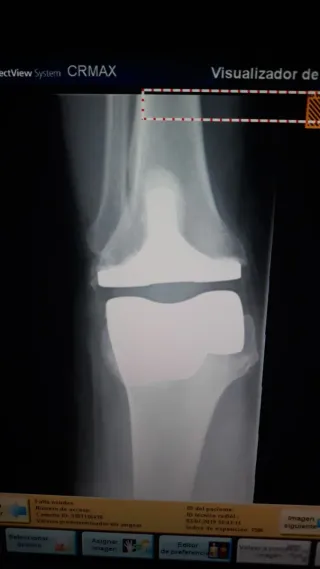

Reveladora Digital Carestream DirectView Max CR

Se vende reveladora digital Carestream DirectView Max CR, equipo de alta fiabilidad diseñado para entornos clínicos con alto volumen de trabajo. Ofrece procesamiento rápido de placas, excelente calidad de imagen y un flujo de trabajo totalmente automatizado. Características principales - Sistema CR de alto rendimiento, ideal para radiología general. - Capacidad de procesar múltiples casetes simultáneamente. - Calidad de imagen Carestream, con algoritmos avanzados de mejora. - Interfaz intuitiva y fácil integración con PACS/RIS. - Diseño robusto, pensado para uso continuo.